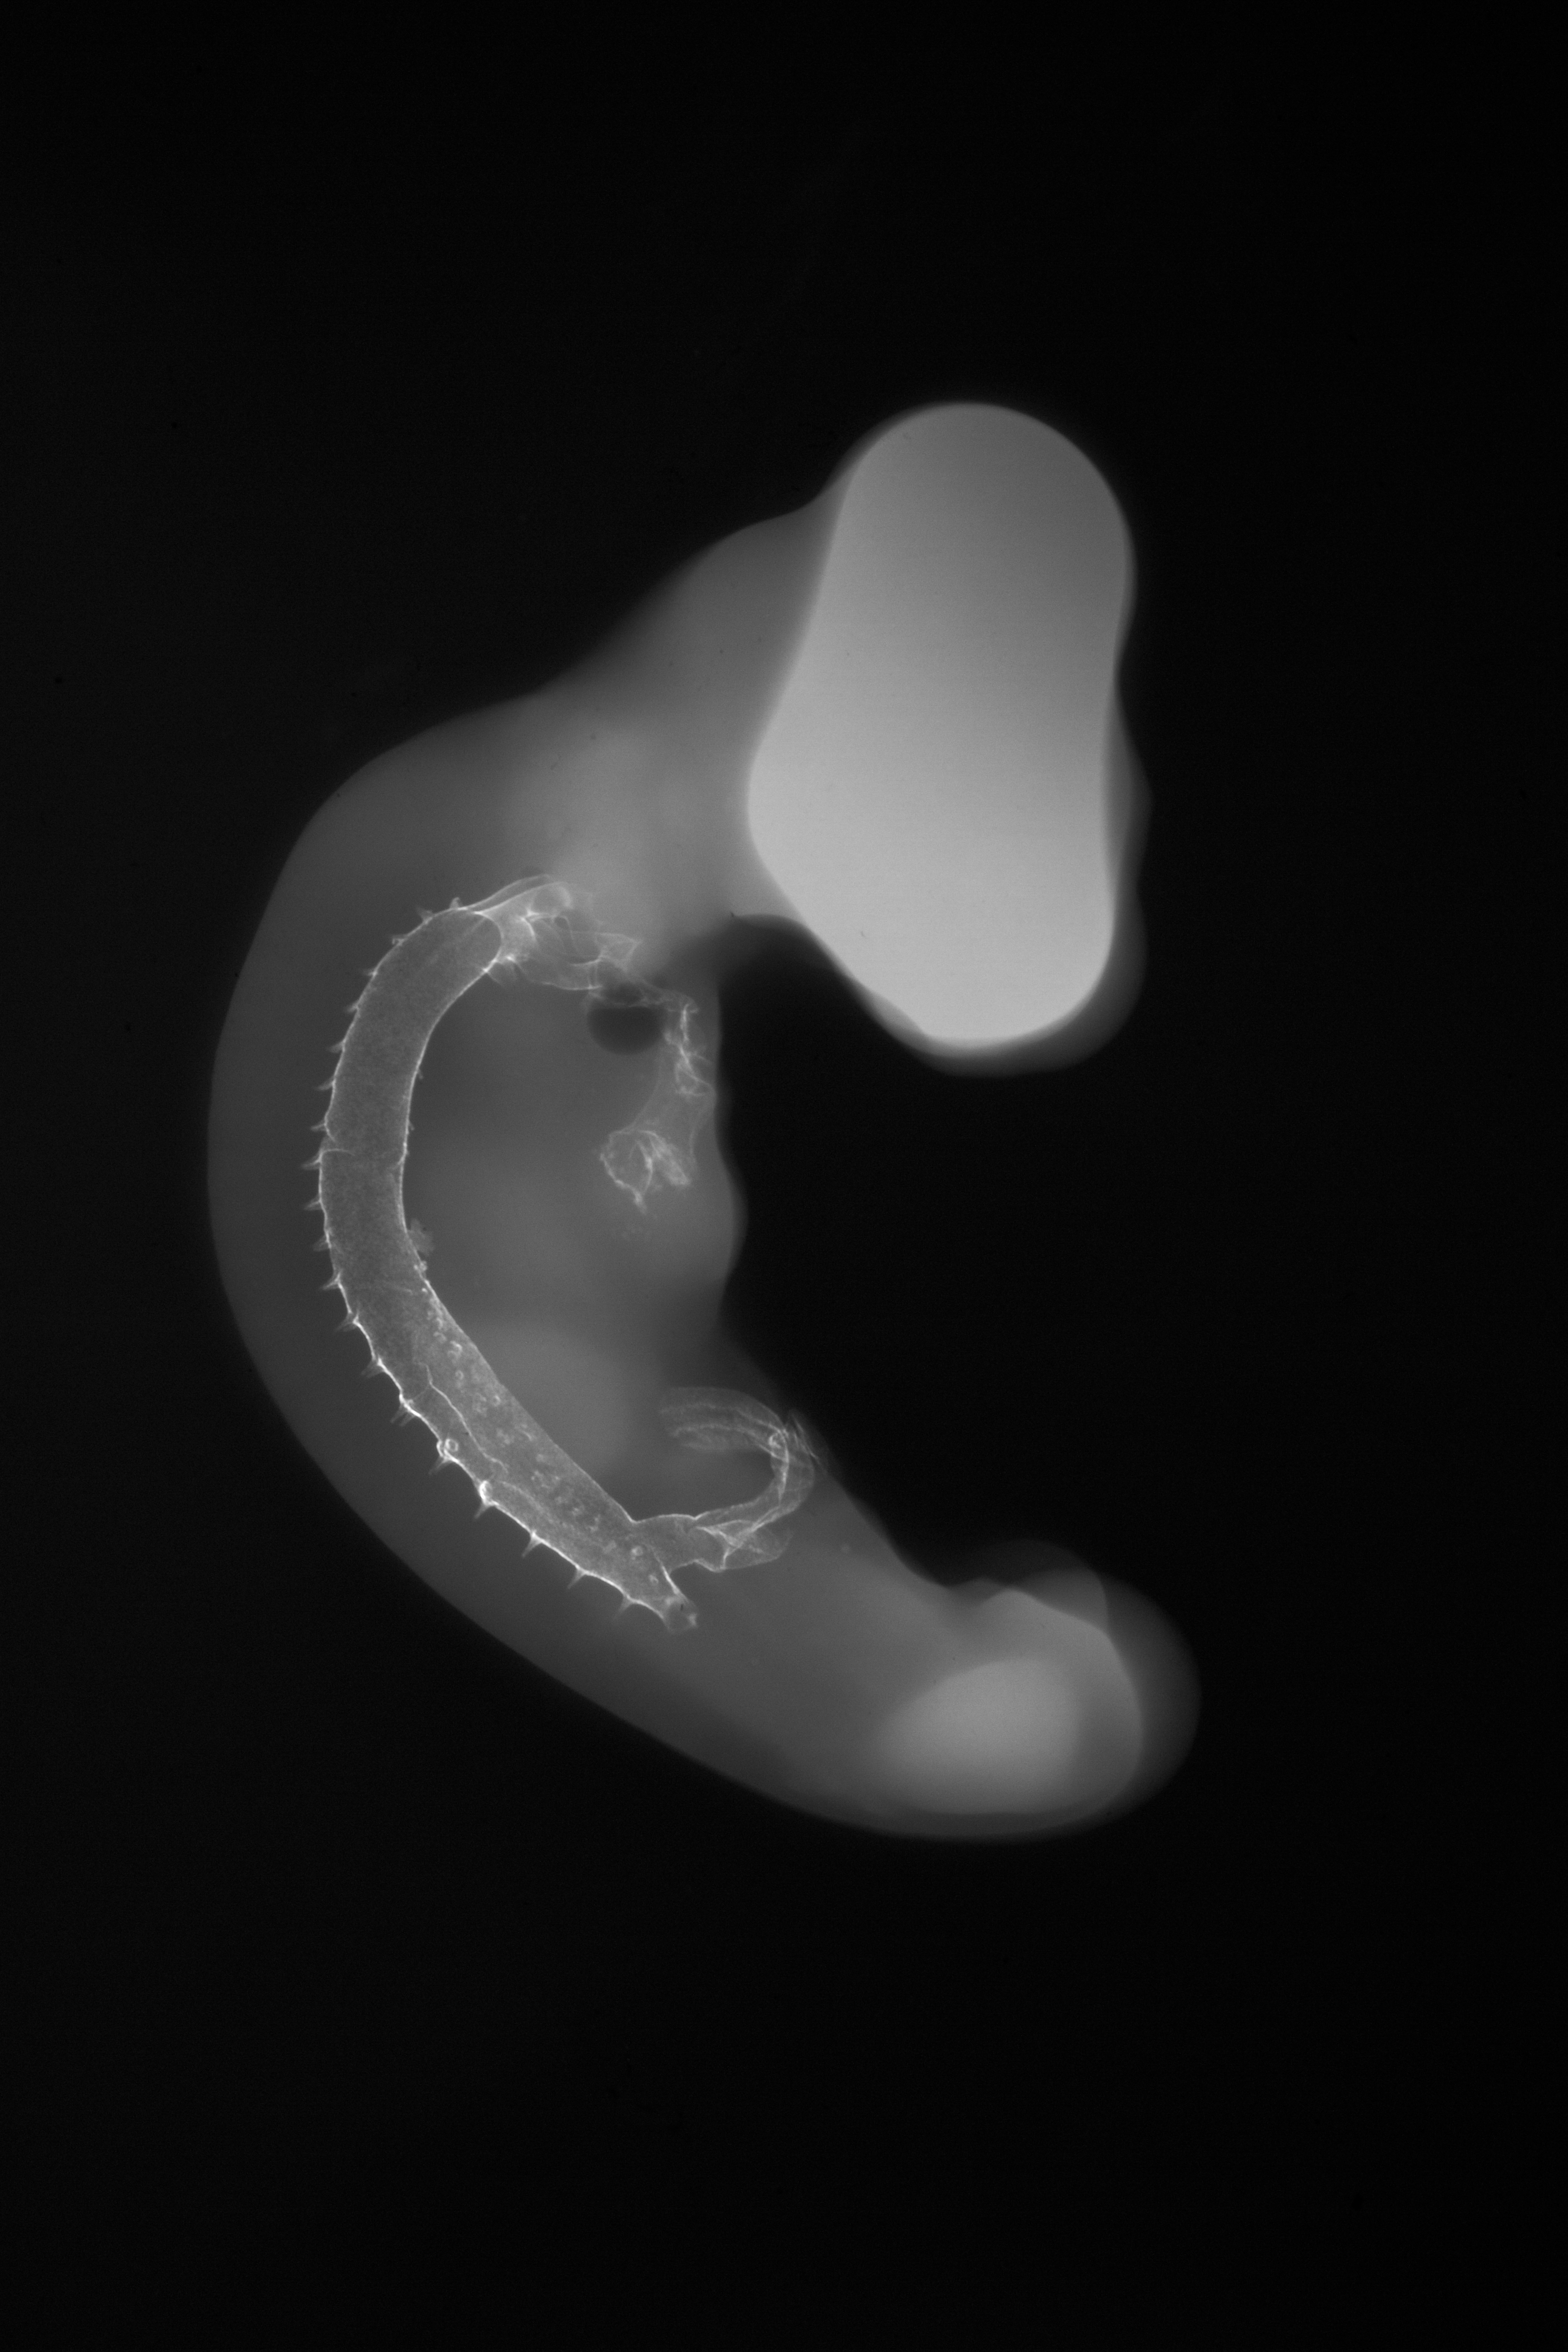

Chick Embryo Microangiography

Hamburger-Hamilton (HH) Stage 23 (approx. 4 days)

X-Ray Micrographs